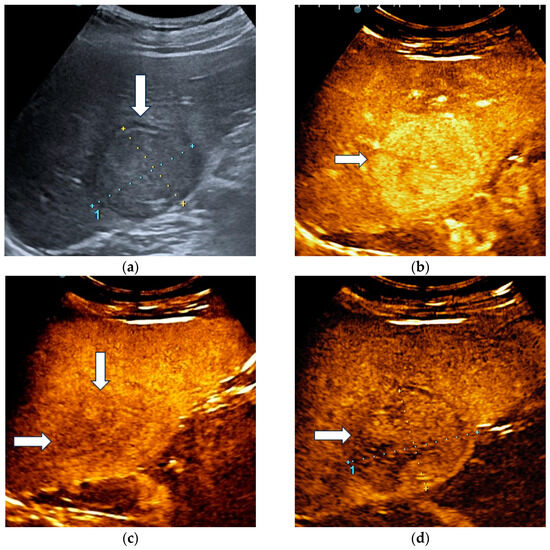

The unblinded and blinded clinicians graded six and, respectively, eight HCCs as non-HCC malignancies, from which two were developed in a non-cirrhotic liver. Three HCC nodules were categorized as indeterminate findings by the reader aware of the clinical data and were considered false negative observations. Four lesions were labelled as indeterminate by the blinded reader. The AI system correctly identified 17 HCCs (Figure 4) and misdiagnosed 6 of them as hemangiomas and one as a non-HCC malignancy.

Figure 4.

A case of hepatocellular carcinoma with typical CEUS enhancement pattern correctly classified by both clinicians and the AI system. B-mode ultrasound showed an isoechoic lesion (arrow), with a peripheral halo, sized 55/44 mm, located in the right hepatic lobe, segment VI (a). In the arterial phase of CEUS, the lesion showed diffuse hyperenhancement (arrow) (b), followed by washout in the late phase (arrows) with onset later than 2 min (c). At four minutes into the late phase of CEUS (arrow), the washout was still mild (d).